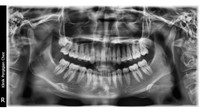

Setelah dilakukan pemeriksaan X-ray, tidak ada tanda-tanda gigi permanen akan tumbuh menggantikan gigi susu itu. (Tangkapan Layar Tiktok/ @le.naqi)

"Dokter gigi kasih tahu saya kalau memang dua gigi itu ya gigi susu dan itu ternyata permanen sampai sekarang," ceritanya yang dikutip dari Mstar, Rabu (14/9/2022). (Tangkapan Layar Tiktok/ @le.naqi)

Dokter gigi kasih tahu saya kalau memang dua gigi itu ya gigi susu dan itu ternyata permanen sampai sekarang, ceritanya yang dikutip dari Mstar, Rabu (14/9/2022). (Tangkapan Layar Tiktok/ @le.naqi)